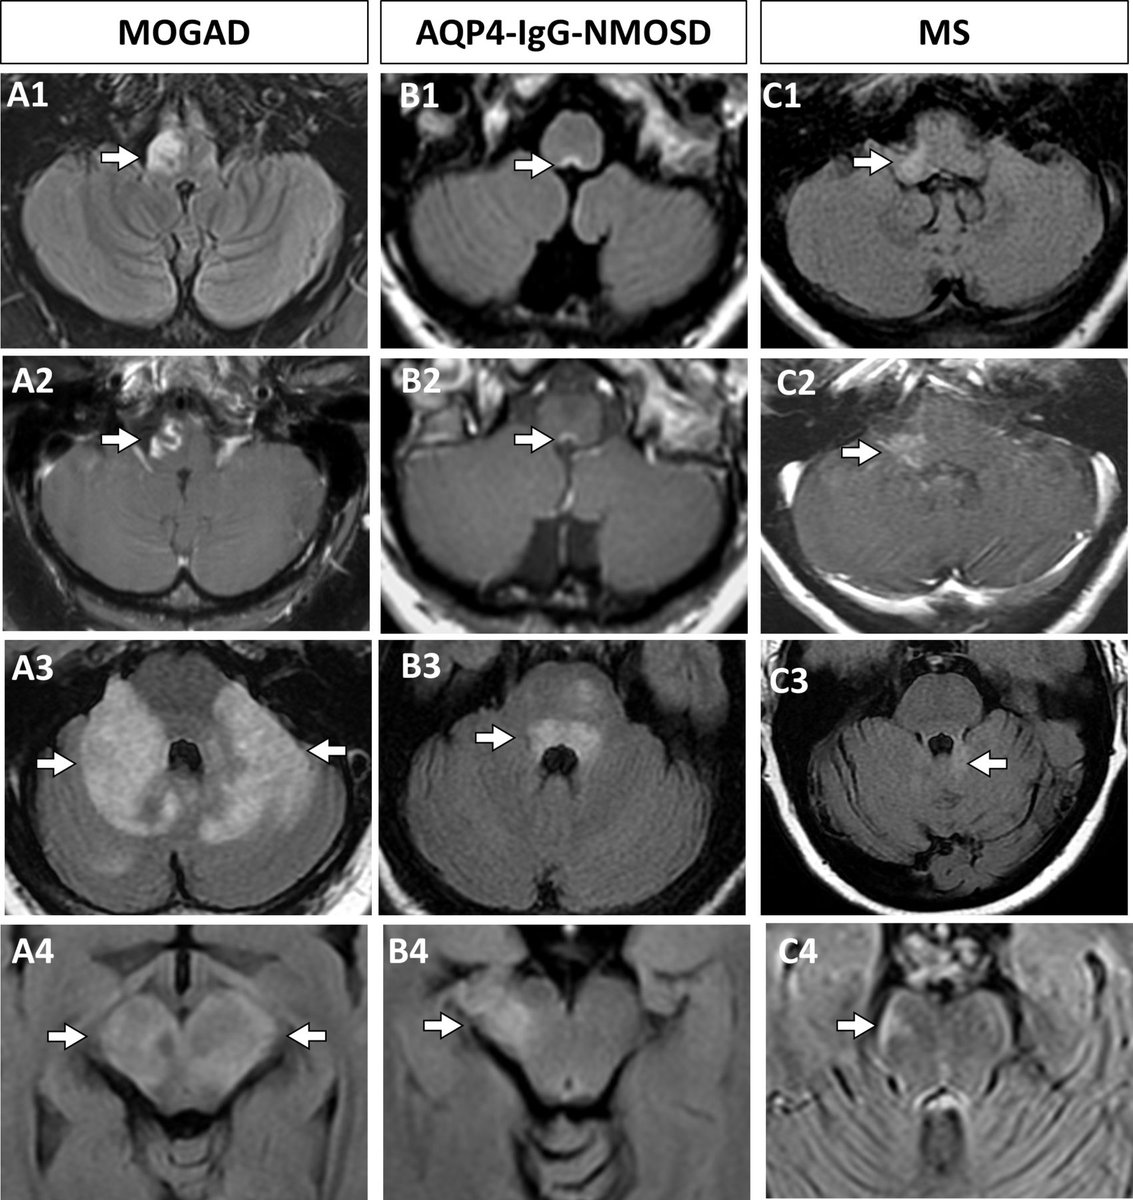

In the posterior fossa, imaging can help distinguish these disorders too.

@SamanthaBanksMD's study below showed lesions diffusely involving the middle cerebellar peduncle favor MOGAD over AQP4-IgG-NMOSD (which more often affects the area postrema) and MS (where short peripheral lesions are more common).